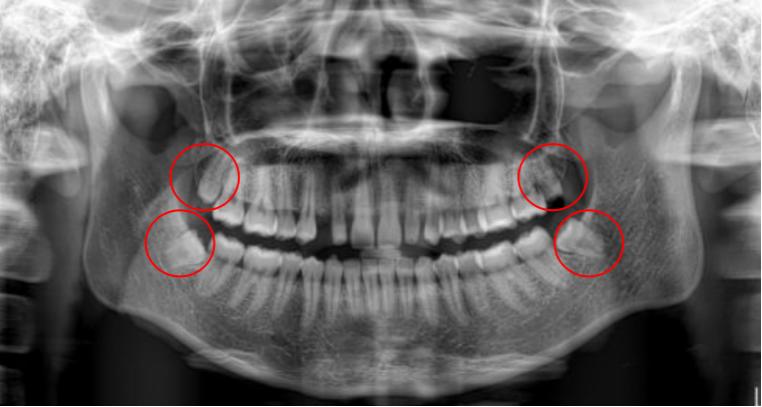

智齿也称第三磨牙,一般在18-25岁左右萌出,是人一生中最后萌出的牙齿,此时人心智基本成熟而得名。

随着人类的进化,头面部的骨骼,肌肉,牙齿也在退化,只是骨头较牙齿退化得快一些。也就是骨头变小的速度大于牙齿数目减少的速度,导致相对较小的骨头容纳不下现在的牙齿,智齿又最后萌出,没有了空间,可能完全阻生,也可能部分或完全萌出。

萌出之初,牙冠和牙肉之间形成空隙。上颌因为智齿靠近软腭,刷牙易引起恶心,下颌智齿靠下颌骨的前方,空间有限,牙刷刷头较难深入,清洁不到位,食物残留,细菌聚集,引发感染,称智齿管周炎。